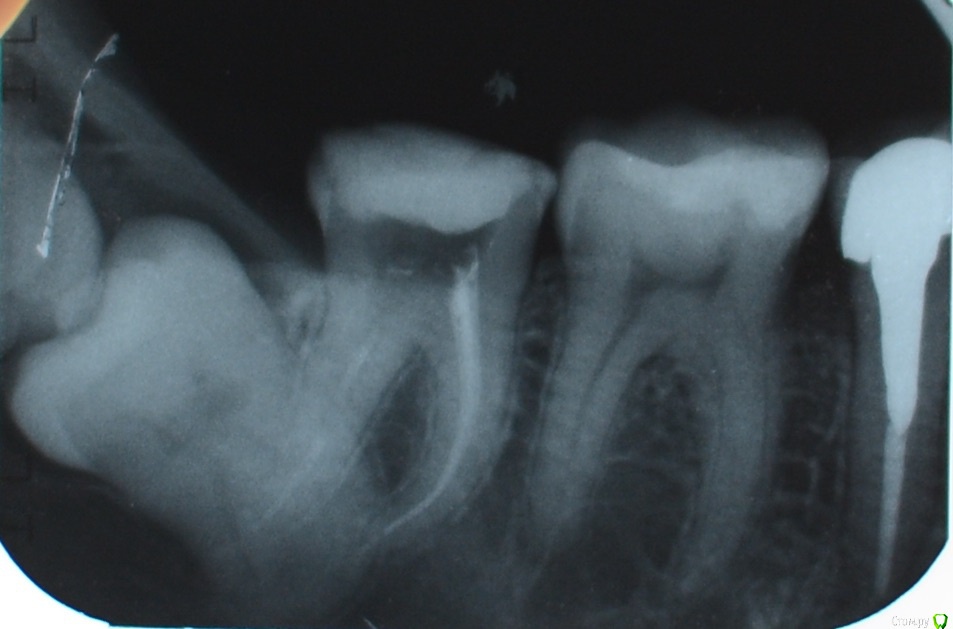

Kitten Опубликовано 22 декабря, 2014 Поделиться Опубликовано 22 декабря, 2014 Добрый день, После лечения глубокого кариеса зуба 4-7 остались только две тонкие стенки, перешла к протезированию. Врач предложил металлокерамику - металлическая культевая вкладка плюс коронка. Перед этим протезировала пятый зуб в другой клинике, обошлось без металла, поэтому засомневалась, стоит ли металлокерамику устанавливать. Специалисты, расскажите, пожалуйста, о плюсах и минусах металлокерамики и об альтернативных вариантах протезирования, если это имеет место. Спасибо! Ссылка на комментарий

SDC Опубликовано 22 декабря, 2014 Поделиться Опубликовано 22 декабря, 2014 Добрый день, После лечения глубокого кариеса зуба 4-7 остались только две тонкие стенки, перешла к протезированию. Врач предложил металлокерамику - металлическая культевая вкладка плюс коронка.Перед этим протезировала пятый зуб в другой клинике, обошлось без металла, поэтому засомневалась, стоит ли металлокерамику устанавливать. Специалисты, расскажите, пожалуйста, о плюсах и минусах металлокерамики и об альтернативных вариантах протезирования, если это имеет место. Спасибо!Простите, а какая конструкция на 5-м зубе предоставленного снимка (Вы об этом 5-м?)В Вашем случае необходимо сделать КТ, для выяснения положения 48 и 49 зубов и прогноза.Возможно, что показано их удаление перед протезированием 47.Культевая вкладка, на мой взгляд, в 47 не нужна. Для восстановления зуба под коронку я бы предложил композитный билдап со штифтом.Возможно протезирование этого зуба любым видом коронок, но предпочтение тонкостенным конструкциям (Преттау или цельнолитая золотая коронка), по причине истонченных стенок зуба. Ссылка на комментарий

Kitten Опубликовано 22 декабря, 2014 Автор Поделиться Опубликовано 22 декабря, 2014 С ходу затрудняюсь сказать о конструкции 5-ого зуба, нужно уточнить (именно он виден на снимке, да). КТ делала, вот ссылка на соседнюю ветку. http://forum.stom.ru/topic/27865-zub-mudrosti-lezhit-vertikalno-udaliatne-udal/ Мнения разные, но специалисты говорят, что 8 и 9 зуб можно удалить, не трогая 7, те продолжать протезирование 7 можно. Ссылка на комментарий

SDC Опубликовано 22 декабря, 2014 Поделиться Опубликовано 22 декабря, 2014 С ходу затрудняюсь сказать о конструкции 5-ого зуба, нужно уточнить (именно он виден на снимке, да). КТ делала, вот ссылка на соседнюю ветку.http://forum.stom.ru/topic/27865-zub-mudrosti-lezhit-vertikalno-udaliatne-udal/ Мнения разные, но специалисты говорят, что 8 и 9 зуб можно удалить, не трогая 7, те продолжать протезирование 7 можно.Дело в том, что при удалениях возможно повреждение коронки 7-го зуба или, что наиболее вероятно, изменится контур десны в области 7-го и край коронки окажется над десной, что не лучшим образом скажется на гигиене и сроках службы коронки 2 Ссылка на комментарий